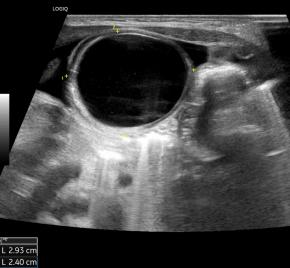

Elastography for the differential diagnosis of malignant versus benign testicular lesions: a meta-analysis

Ziwei Lin, Rui Lin, Huaiyu Wu, Linghu Wu, Jieying Zeng, Jinfeng Xu, Fajin Dong